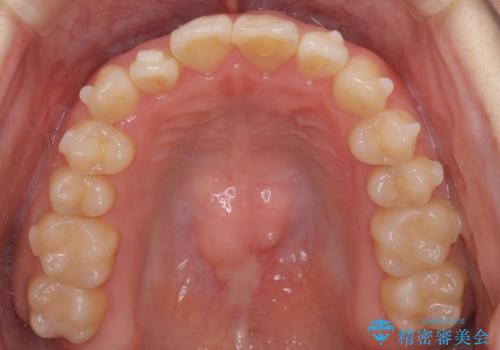

【インビザライン】前歯のがたつきを目立たない装置で治療

- 前歯の叢生を主訴に来院されました。目立たない装置を希望されたためインビザラインで治療を行いました。

IPRと拡大をし、叢生を治しました。右上2番は反対咬合でしたが短期間できれいに治りました。